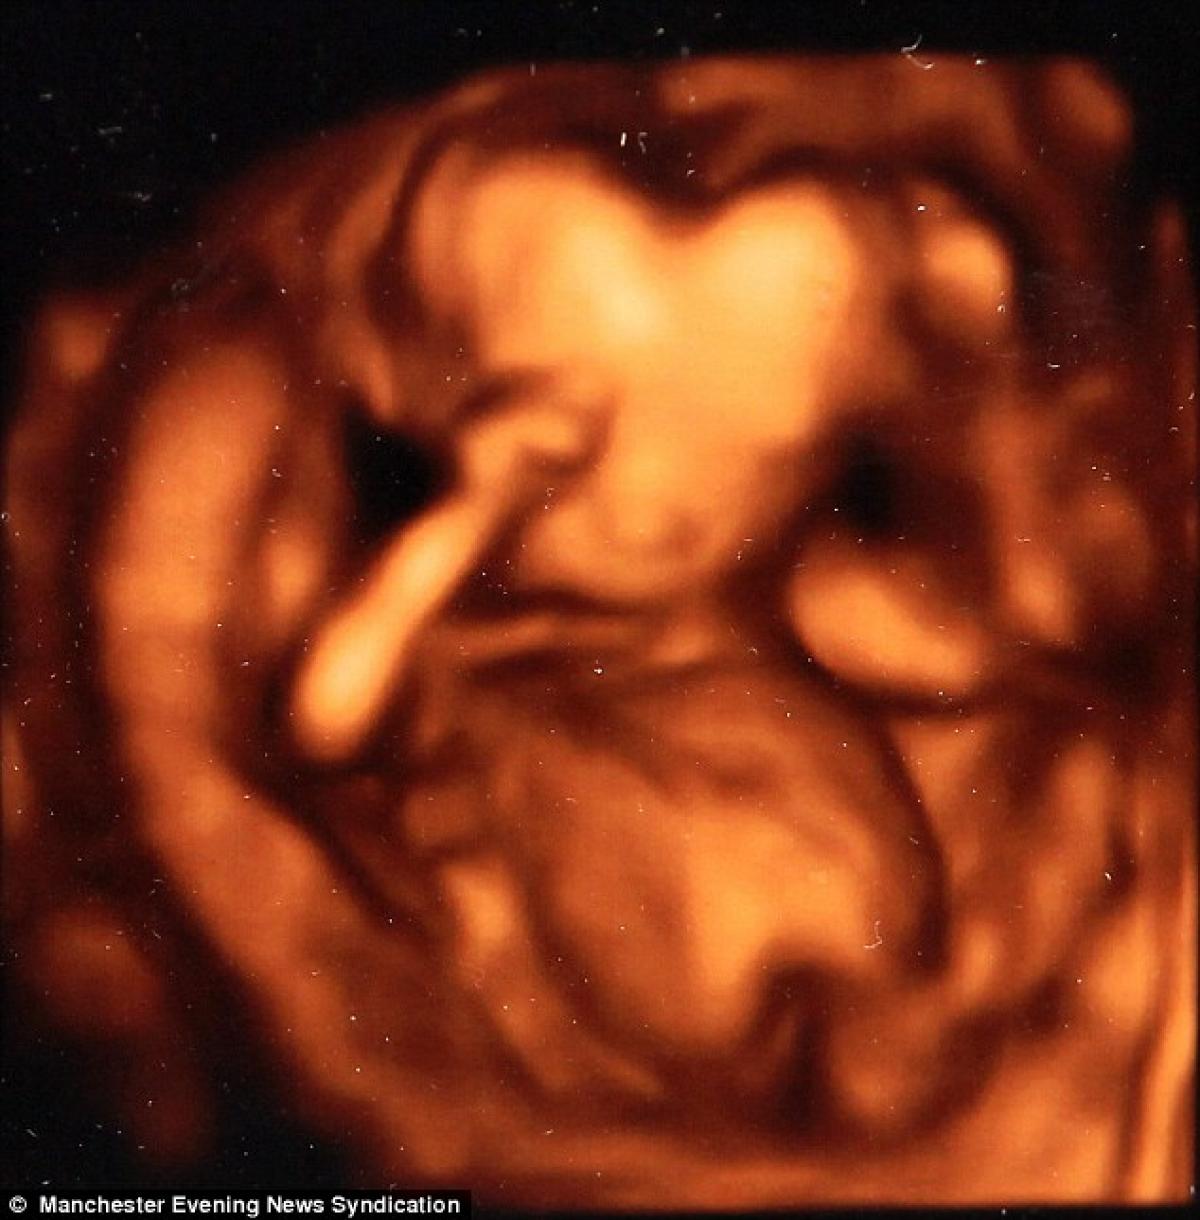

Imaginea care a șocat medicii! Bebelușul cu un cap în formă de inimă

Scanarea 3D a arătat ceva complet neașteptat - micuțul Logan avea un cap în formă de inimă! Alarmați, părinții au cerut explicații de la medicii luați prin surprindere. Din fericire, aceștia și-au dat curând seama că forma inedită se datora procesului de formare a copilului și posibil, a unghiului din care a fost făcută imaginea.

Un cap în formă de inimă e ceva unic, mama mea a observat prima acest lucru”, spune Beverly, mama micuțului. În septembrie, Logan s-a născut perfect normal, imaginea devenind o amintire foarte specială.